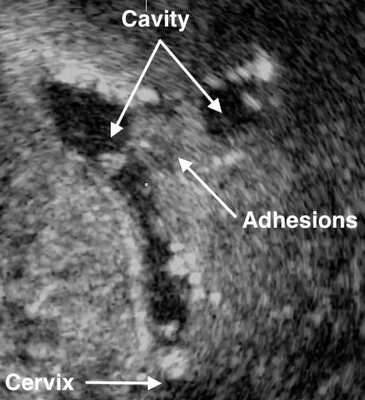

УЗИ малого таза при синдроме Ашермана малоинформативно; эхоскопическая картина может быть представлена нерегулярными конурами эндометрия, в случае гематометры - анэхогенным образованием в полости матки. Проведении гистеросальпингоскопии позволяет более четко определять наличие внутриматочных сращений.

Наиболее полная картина представляется при выполнении гистеросальпингографии и гистероскопии. Гистеросальпингография выявляет одиночные либо множественные дефекты наполнения, имеющие лакунообразную форму и различные размеры. При плотных множественных внутриматочных синехиях полость матки на рентгенограмме выглядит многокамерной, с мелкими, соединяющими отдельные камеры протоками. Однако нередко гистеросальпингография сопровождается ложноположительными результатами из-за наличия в матке слизи, искривлений, обрывков эндометрия. При эндоскопической гистероскопии внутриматочные синехии определяются как белесоватые бессосудистые тяжи разной плотности и длины, соединяющие стенки матки, обнаруживается облитерация или деформация полости матки.

- Ультразвуковое исследование. Если есть спайки, то на снимках видны эхогенные, нерегулярные эксцентричные линейные сигналы — беловатые плотные участки рубцовой ткани или локальное истончение эндометрия. Исследование проводят в лютеиновую фазу (период с момента овуляции и до начала менструаций).

- Соногистерография — ультразвуковое исследование, во время которого в полость матки вводят физиологический раствор.